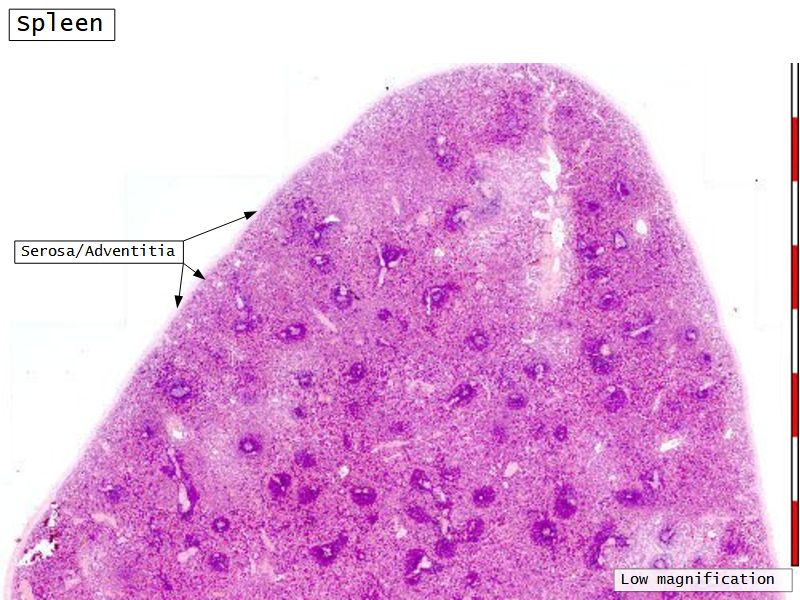

Fill in all the missing labels, and assess as you move through the slides. Answers on the down slide. It is important to do this using pen and paper, and not just glance through the images.